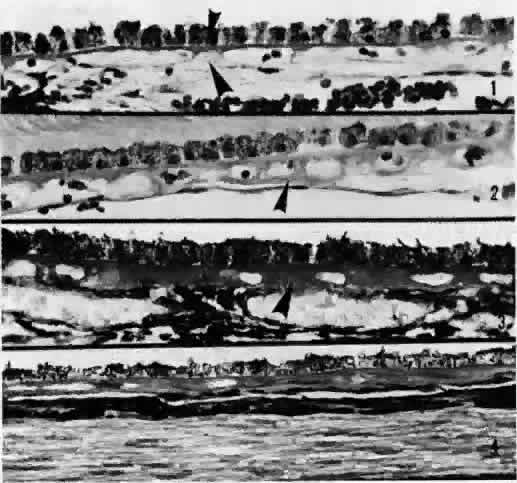

without intervening venule drainage. Torczynski and Tso27 reported on the architecture of the choriocapillaris in the posterior

pole after examining choroidal flat preparations and transverse and oblique

histologic sections (Figs. 21, 22, and 23). They described the overall appearance of the posterior choriocapillaris

as a series of adjoining lobules that was striking in some preparations

and subtle in others. The center of the lobule consisted of a single

precapillary arteriole rimmed in a thick mantle of collagen measuring 15 to 25 μm

and opening perpendicularly or curvilinearly into

a capillary bed that radiated an average distance of 300 to 400 μm

before changing from a radial to a circumferential direction. The circumferential

capillaries in the periphery of the lobule were wider and

converged from several directions, forming star-like or dendritiform configurations

in the plane of the choriocapillaris. Venular openings, outward

bulgings of the external choriocapillaris called atria, measured 30 to 37.5 μm and were present singly and in linear sequences

underlying the circumferential capillaries. The often incomplete lobules

varied in their geometric configuration, having three to six sides

and ranging in area from 420 × 605 μm to 800 × 1200 μm. The

lobular unit was thought to provide a preferred outflow route

via the perimeter of postcapillary venules so that cross-flow from

lobule to lobule would not normally occur, and thus the precapillary

arteriole would function as an end-arteriole.  Fig. 21. Flat preparation of choriocapillaris, posterior pole. A. Arrowheads indicate oval openings to the postcapillary venules. The area